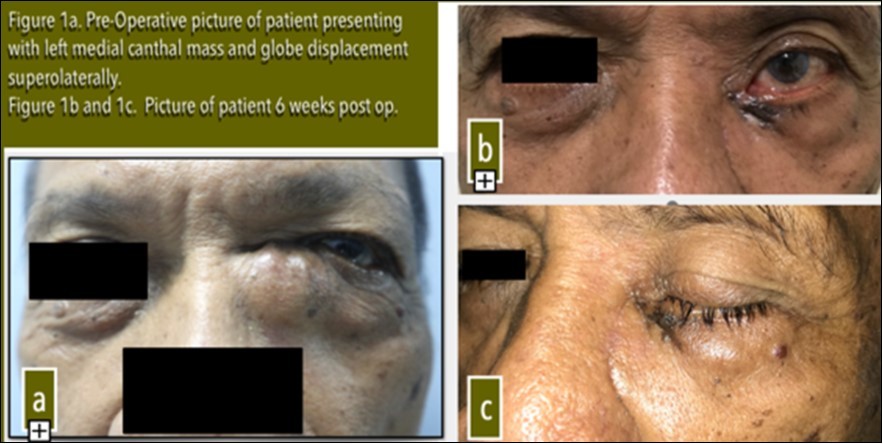

Ophthalmologic examination revealed a 20x20 mm firm and fixed mass at the left medial canthal area with globe displacement superolaterally [Figure 1a].

Figure 1a.Pre-Operative picture of patient presenting with left medial canthal mass and globe displacement superolaterally. Figure 1b and 1c. Picture of patient 6 weeks post op.

Post-operative recovery was uneventful with unchanged visual acuity and extraocular muscle movement. Patient was asymptomatic but exhibited mild ectropion [Figure 1b].